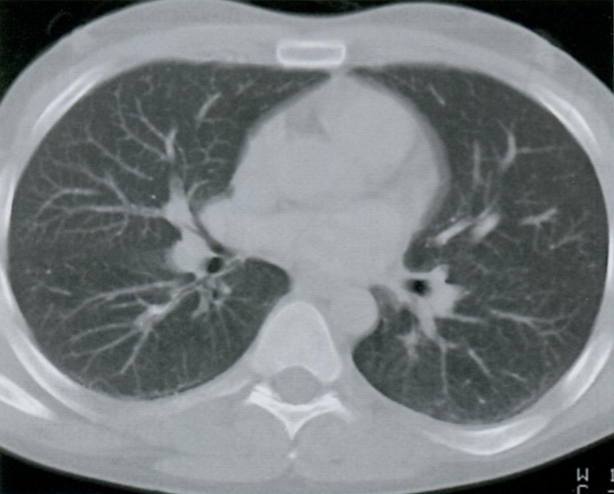

КТ грудной клетки №3

Назовите все анатомические структуры, которые Вы знаете, на данном КТ срезе (10).

Найдите грудные позвонки и грудину. Затем верхнюю полую вену, восходящую и нисходящую аорту, легочный ствол, левое предсердие и легочные сосуды, непарную вену и пищевод.

A

26 - грудные позвонки

24 - грудина

1 - верхняя полая вена

7 - восходящая аорта

9 - легочный ствол

3 - левое предсердие

10 - сосуды легких

8 - нисходящая аорта

15 - непарная вена

16 - пищевод

Синим цветом отмечены номера сегментов.